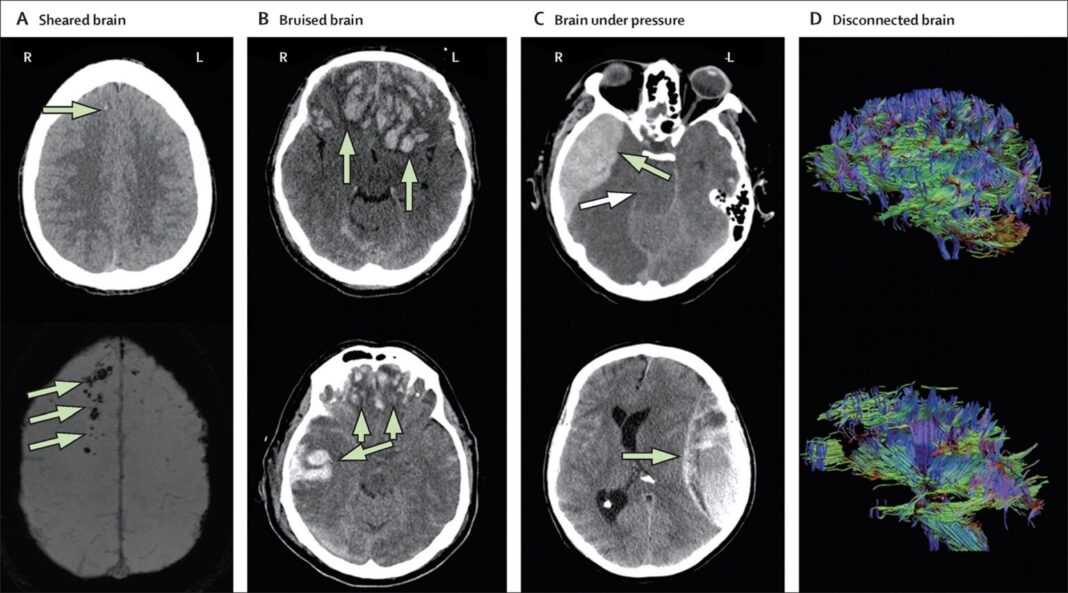

Οι Times συγκρίνουν τις σοβαρές εγκεφαλικές βλάβες με ισχυρούς σεισμούς, αλλά αντί να γκρεμίζονται γέφυρες και κτίρια, τα οστά μας σπάνε καθώς αργότερα εκρήγνυνται αιμορραγίες με ακατέργαστα επώδυνα τραύματα στο πρόσωπο.

“Αλλά οι ήπιοι εγκεφαλικοί τραυματισμοί είναι μικρότεροι σεισμοί: Τα βιβλία πέφτουν από τα ράφια, τα βάζα είναι σπασμένα. Είναι πιο δύσκολο να ερευνήσεις τη ζημιά και εύκολο να χάσεις ό,τι έχει σπάσει, αλλά κάτι δεν πάει καλά”, ανέφερε η εφημερίδα.